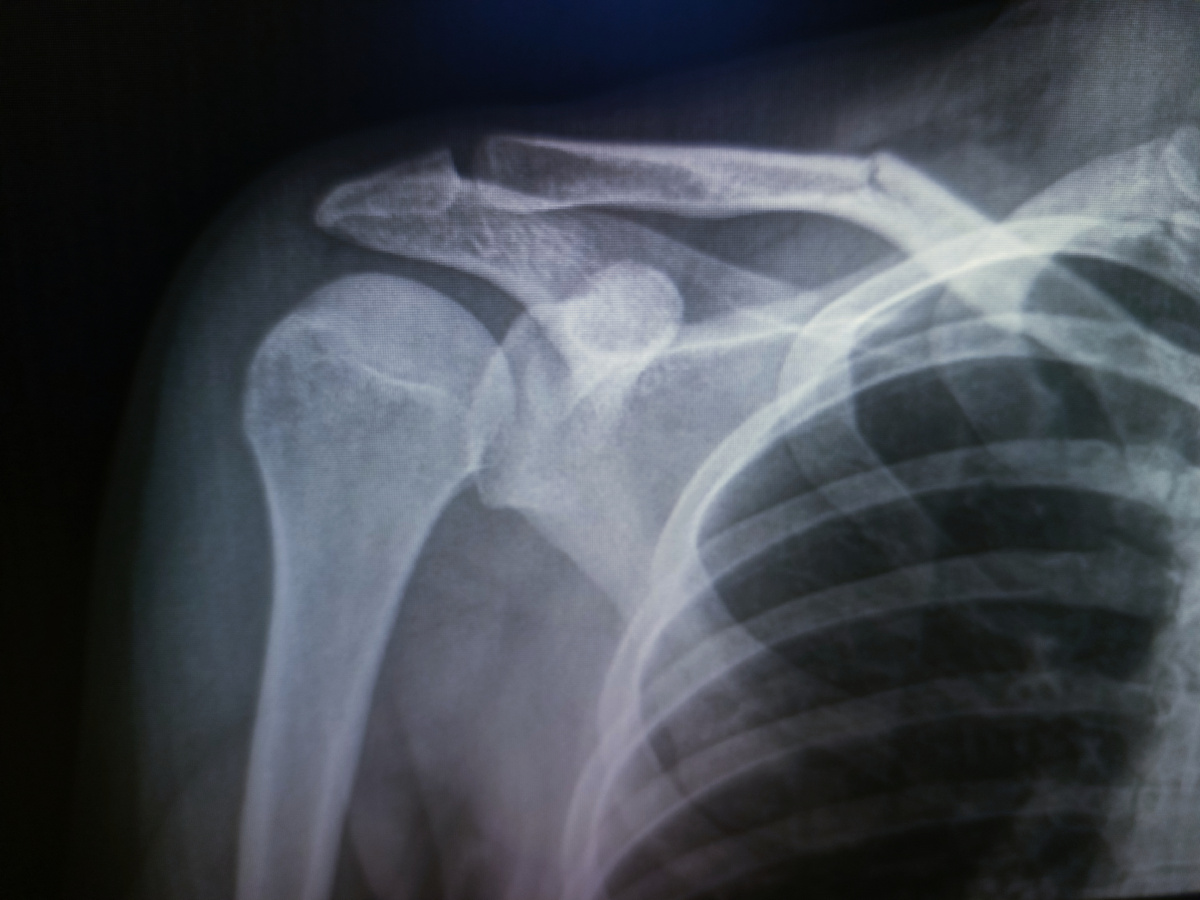

Пришел парень, 20 лет, на снимоктАКС(акромиально-ключичного сочленения).

А по нему видно, что бугорок кости ключицы сломан, глаз у меня на переломы с таким опытом наметан.

Чтобы вы понимали акромиально-ключичное сочленение находится возле сустава, никак не посередине кости.

Позже пришел на контроль с кольцами Дельбе.

Поставят ему пластину, тем более, что перелом без сильного смещения.